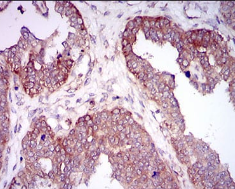

IHC    1/200 - 1/1000

Species Reactivity :   Human,Mouse,Rat,Monkey

Immunogen:    Purified recombinant fragment of human HAS2 (AA: 67-170) expressed in E. Coli.